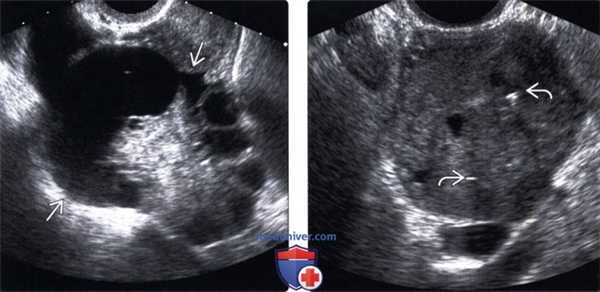

2. УЗИ при метастазах в яичники и опухоли Крукенберга:

• Серошкальное ультразвуковое исследование:

о Опухоль яичника

о Солидная или кистозно-солидная:

- Редко однокамерная киста

- Может осложняться кровотечением

- Может имитировать муцинозную диссеминированную цистаденокарциному

• Цветовая допплерография:

о Васкуляризация в солидных опухолях варьирует

(Левый) На сагиттальном трансвагинальном УЗ срезе у женщины 63 лет с раком прямой кишки в анамнезе визуализируется крупная солидно-кистозная опухоль правого яичника.

(Правый) На продольном трансвагинальном УЗ срезе визуализируется крупное солидное новообразование придатков у пациентки с раком желудка. Обратите внимание на мелкие кальцинаты, которые редко наблюдаются в муцинозных аденокарциномах желудка.